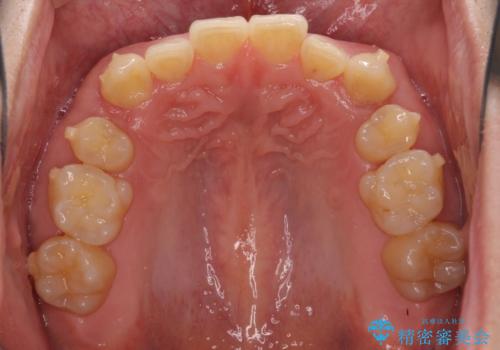

- 上顎の八重歯と前歯のデコボコを気にして来院された患者様です。

八重歯の移動量が多く、インビザライン単体での治療は困難と判断し、補助装置により八重歯移動後にインビザラインを用いることとしました。